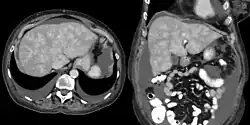

Stauungsleber

Die Stauungsleber ist eine durch eine Blutstauung hervorgerufene Krankheit der Leber. Grund für den verminderten venösen Blutabfluss aus der Leber kann ein Hindernis (z. B. Tumor, Thrombose) zwischen Leber und rechter Herzhälfte sein. Auch kann das Herz selbst die Ursache für den Rückstau sein (zum Beispiel ein Panzerherz, Pericarditis constrictiva).

Durch den Blutstau kommt es zur Ausbildung von Stauungsstraßen innerhalb des Leberläppchens. Diese Stauungsstraßen schließen ein periportales Feld ein (Umkehr der Läppchenstruktur). Durch Nahrungsmangel der Hepatozyten (Leberzellen) kommt es zum Zelluntergang um die Zentralvene des Leberläppchens (Atrophie). Ebenfalls tritt eine gelblich imponierende Verfettung ein. Wird eine solche Leber nach dem Tod aufgeschnitten, zeigt sich ein Bild, das an Herbstlaub oder Muskatnüsse erinnert („Muskatnussleber“ oder „Herbstlaubleber“).